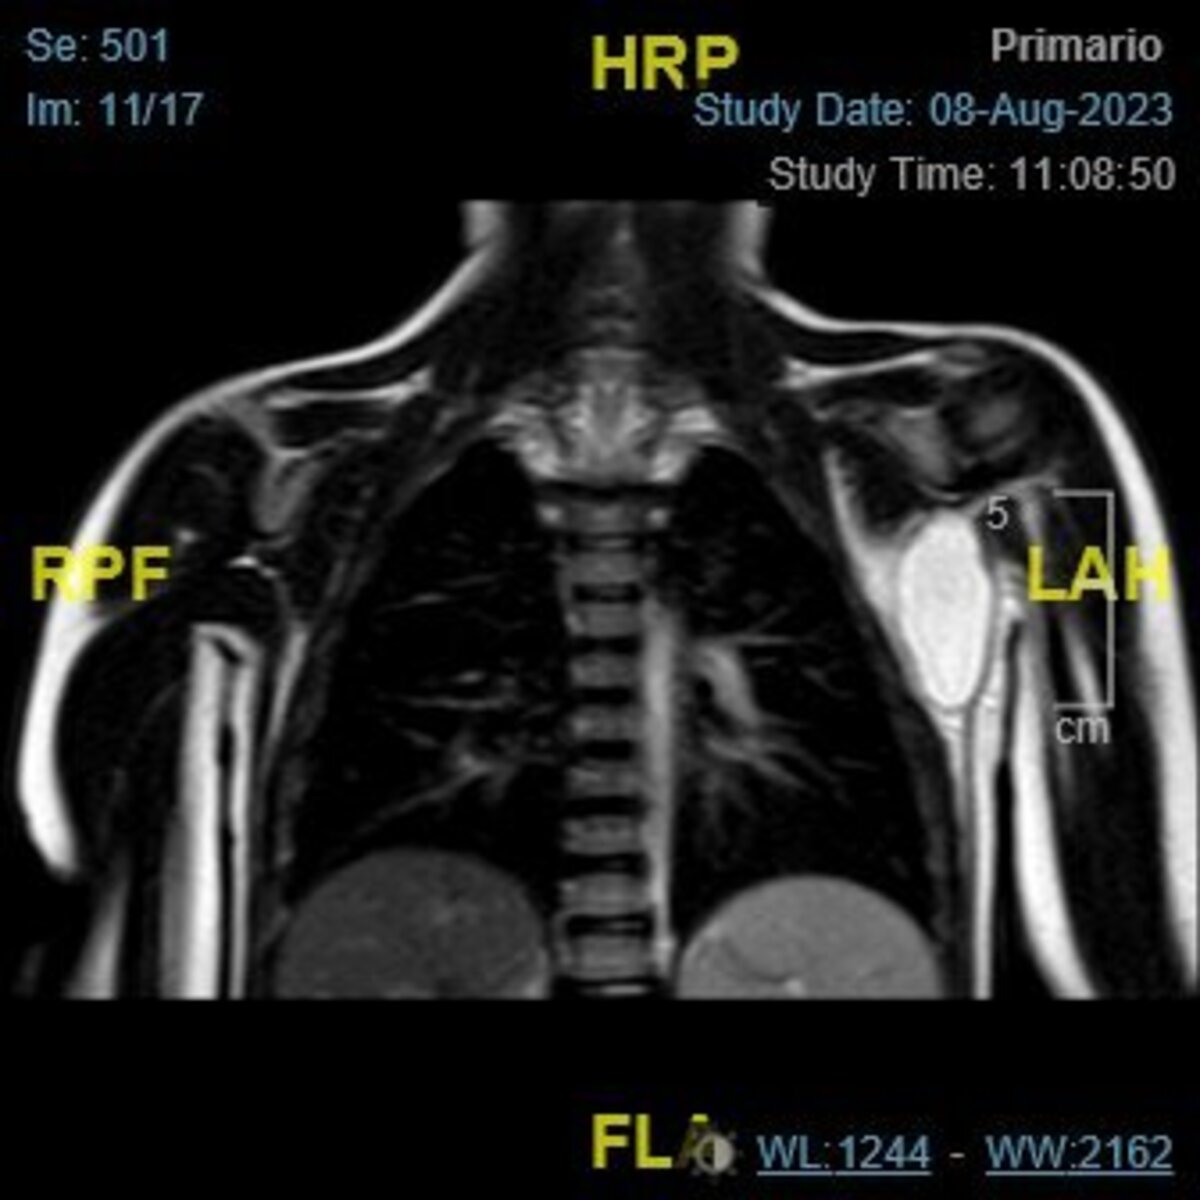

Niña de cuatro años que acude a Urgencias por presentar desde hace 30 horas una tumoración dolorosa en la región axilar izquierda (Figura 1). Asocia pico febril de 38,5 °C sin otra sintomatología. Sin antecedentes de interés. Se realiza analítica sanguínea, en la que destaca un leve aumento de reactantes de fase aguda, y una ecografía que muestra una colección heterogénea con septos en su interior. No se visualiza líquido articular. Se solicita resonancia magnética (Figura 2).

Figura 2. Resonancia magnética nuclear: colección quística con septos internos en la región axilar izquierda, de bordes bien definidos, predominantemente hiperintensos en secuencias T2/FLAIR. Asocia aumento de señal de las partes perilesionales.